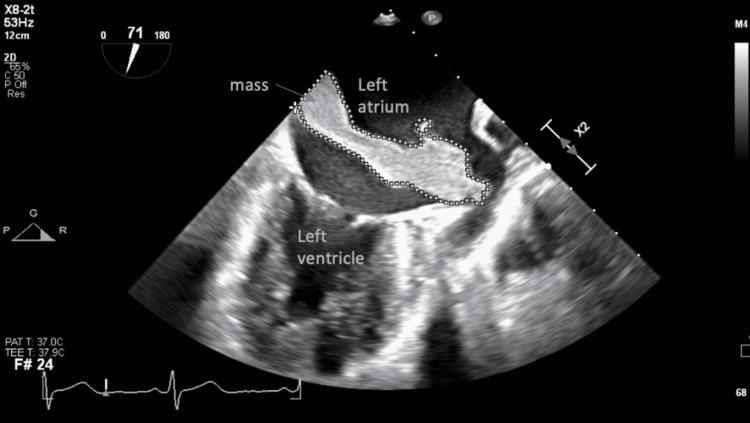

A 75-year-old Caucasian female with a past medical history including insulin-dependent diabetes mellitus, hypertension, and dyslipidemia, presented to the emergency room for having palpitations for three weeks. Echocardiography revealed a very large left atrial mass mimicking myxoma. Mass was excised and examined by pathology, revealing a mural thrombus. A mural thrombus is not an uncommon mass found in the left atrium. However, it does not often present symptomatically, strongly mimics an atrial myxoma on cardiac imaging, and has rarely ever been reported to be greater than seven centimeters in any dimension. We present a case of a 75-year-old Caucasian woman with a massive, symptomatic cardiac thrombus masquerading as a myxoma on imaging.

一名75岁的白种女性,既往有胰岛素依赖型糖尿病、高血压和血脂异常病史,因心悸三周就诊于急诊室。超声心动图显示左心房有一个非常大的肿块,类似黏液瘤。肿块被切除并送病理检查,结果显示为壁血栓。壁血栓在左心房并不罕见。然而,它通常没有症状,在心脏成像上与心房黏液瘤极为相似,而且从未有过任何维度大于7厘米的报道。我们报告一例75岁白种女性病例,其心脏有一个巨大的、有症状的血栓,在影像学上伪装成黏液瘤。